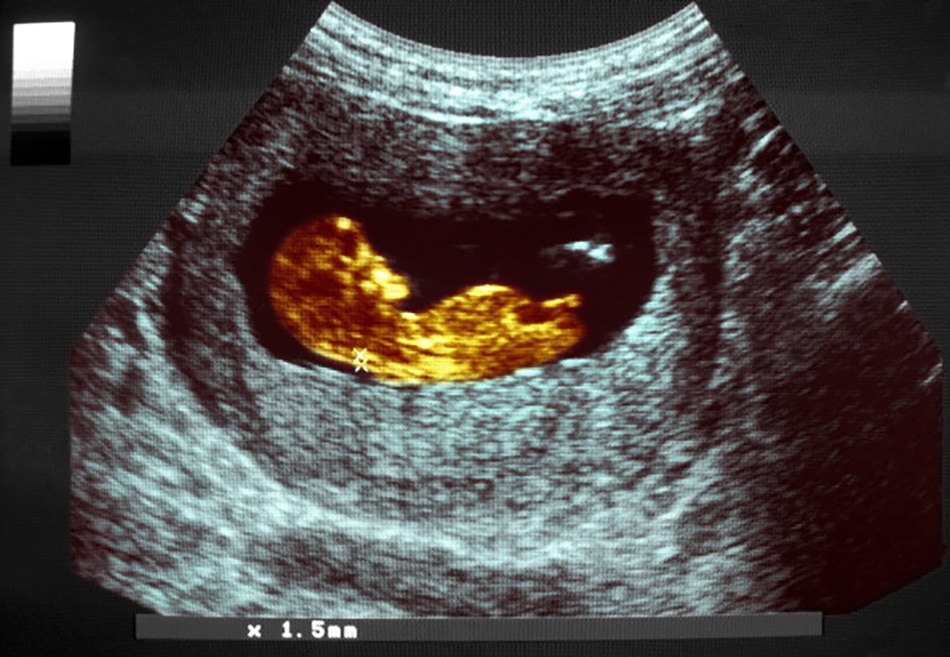

फर्स्ट ट्राइमेस्टर स्क्रीनिंग

किसी महिला की 11 से 13 हफ्तों की प्रेग्नेंसी के दौरान एक विशेष अल्ट्रासाउंड स्कैन कराया जा सकता है, जिसे न्यूकल ट्रांसल्यूसेंसी (एनटी) स्कैन कहा जाता है. इस स्कैन में मापा जाता है कि गर्भस्थ शिशु की गर्दन के पीछे की तरफ त्वचा के नीचे कितना तरल है. इससे डाउन सिंड्रोम के खतरे का पता लगाया जाता है.

डबल मार्कर टेस्ट जरूरी

इस जांच में एचसीजी (hCG, ह्यूमन कोरियोनिक गोनाडोट्रॉफिन) और पैप-ए (PAPP-A, प्रेग्नेंसी एसोसिएटेड प्लाज्मा प्रोटीन) के स्तरों को मापा जाता है. अगर किसी महिला के गर्भ में डाउन सिंड्रोम से ग्रस्त शिशु पल रहा हो, तो उसके खून में एचसीजी और पैप-ए दोनों का असामान्य स्तर पाया जाएगा. अगर कुशल डॉक्टर और अच्छी गुणवत्ता की स्कैनिंग मशीन से ये टेस्ट होते हैं तो ये काफी सटीक होते हैं.